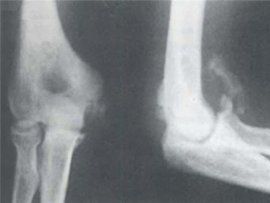

(1)軟骨性骨化(cartilaginous ossification,endochondral ossification):首先形成玻璃軟骨組織,再被骨組織所置換,是在大部分骨中能見到的類型。按此型生成的骨有軟骨性骨、置換性骨等稱。

(2)結締組織性骨化(intramembranousossification)或纖維性骨化(fibrous ossification):在纖維性結締組織內,直接形成骨組織的類型,在部分頭骨中可見到。按此類型所生成的骨稱為結締組織骨、膜骨、被蓋骨等。這兩種形式骨化時的造骨細胞,是通過成軟骨細胞或成纖維細胞行二次性的轉化,還是由其周邊未分化的細胞直接分化所成,尚不清楚。造骨細胞逐漸被包埋在由其本身所形成的膠原纖維並伴有鈣質沉著的基質內,而成為休止型的骨細胞。在造骨細胞骨化的同時,另一方面具有同一來源的多核細胞的破骨細胞對纖維和基質通過吞噬而破壞,由於兩種相反的活動,同時通過骨的生長,再造,使骨緻密化,以及進行血中鈣、磷水平的調整。破骨細胞的刺激和抑制分別與甲狀旁腺激素和降(血)鈣素有關。

骨的形成過程,在膜狀骨或軟骨的基礎上,首先在中心部有鈣鹽沉著形成骨化點,由此向周圍產生新骨質,外被以骨膜,新產生的骨質不斷破壞原來的類骨質,形成髓腔並逐漸改變外形轉變成硬骨質的狀況。